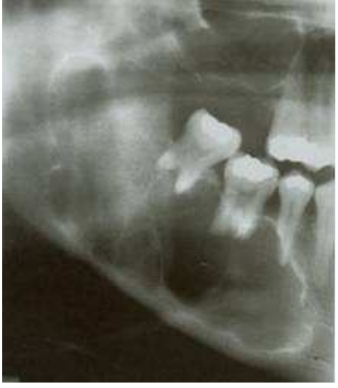

74.一位40歲男性患者,主訴右側下顎部腫大造成顏面畸形,從X光片(如下圖)可見到一多房 性、有明顯骨中隔(bony septa)之放射線透性(radiolucent)影像,自右下顎小臼齒延伸 到上升枝,第二小臼齒有明顯牙根吸收現象,第一、二大臼齒有部分牙根吸收情形,下列何 者是優先考慮的診斷?

(A)造釉細胞瘤(ameloblastoma) (B)骨內血管瘤(central hemangioma) (C)腺瘤樣齒源性瘤(adenomatoid odontogenic tumor) (D)成骨細胞瘤(osteoblastoma)